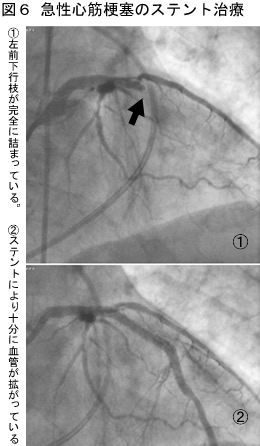

図6は、実際に急性心筋梗塞症でステント治療を行なった患者さんの写真です。

最近ではバルーンによる拡張だけでなく、ステント(金属製網状チューブ)を留置する方法が一般的になって きました。バルーンの表面にあらかじめ、ステンレスやコバルトなどの金属性の網状の筒をかぶせておき、バルーンを拡げたときに、その筒が血管の内腔を押し 拡げ、拡げた状態で血管を維持するという方法です。バルーンだけだと、拡げた冠動脈の部位に大きな傷ができ(冠動脈解離)、結果としてその場所が詰まって しまう(急性冠閉塞)ことがあります。ステントを使うことにより、再度詰まったり狭くなったりするのを減らすことができます(図5)。